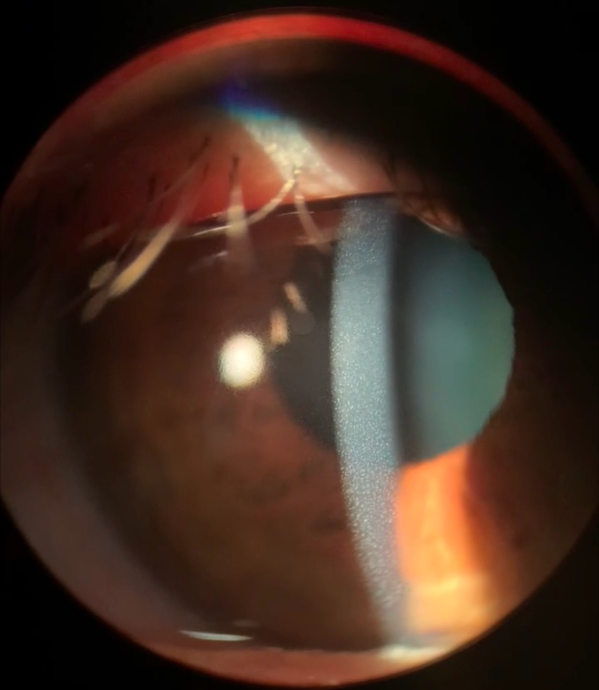

The popular cosmetic trends in today’s world including eyelash curling, brow tinting, tubing mascara, and more!

Ocular complications secondary to some dangerous ingredients in many products